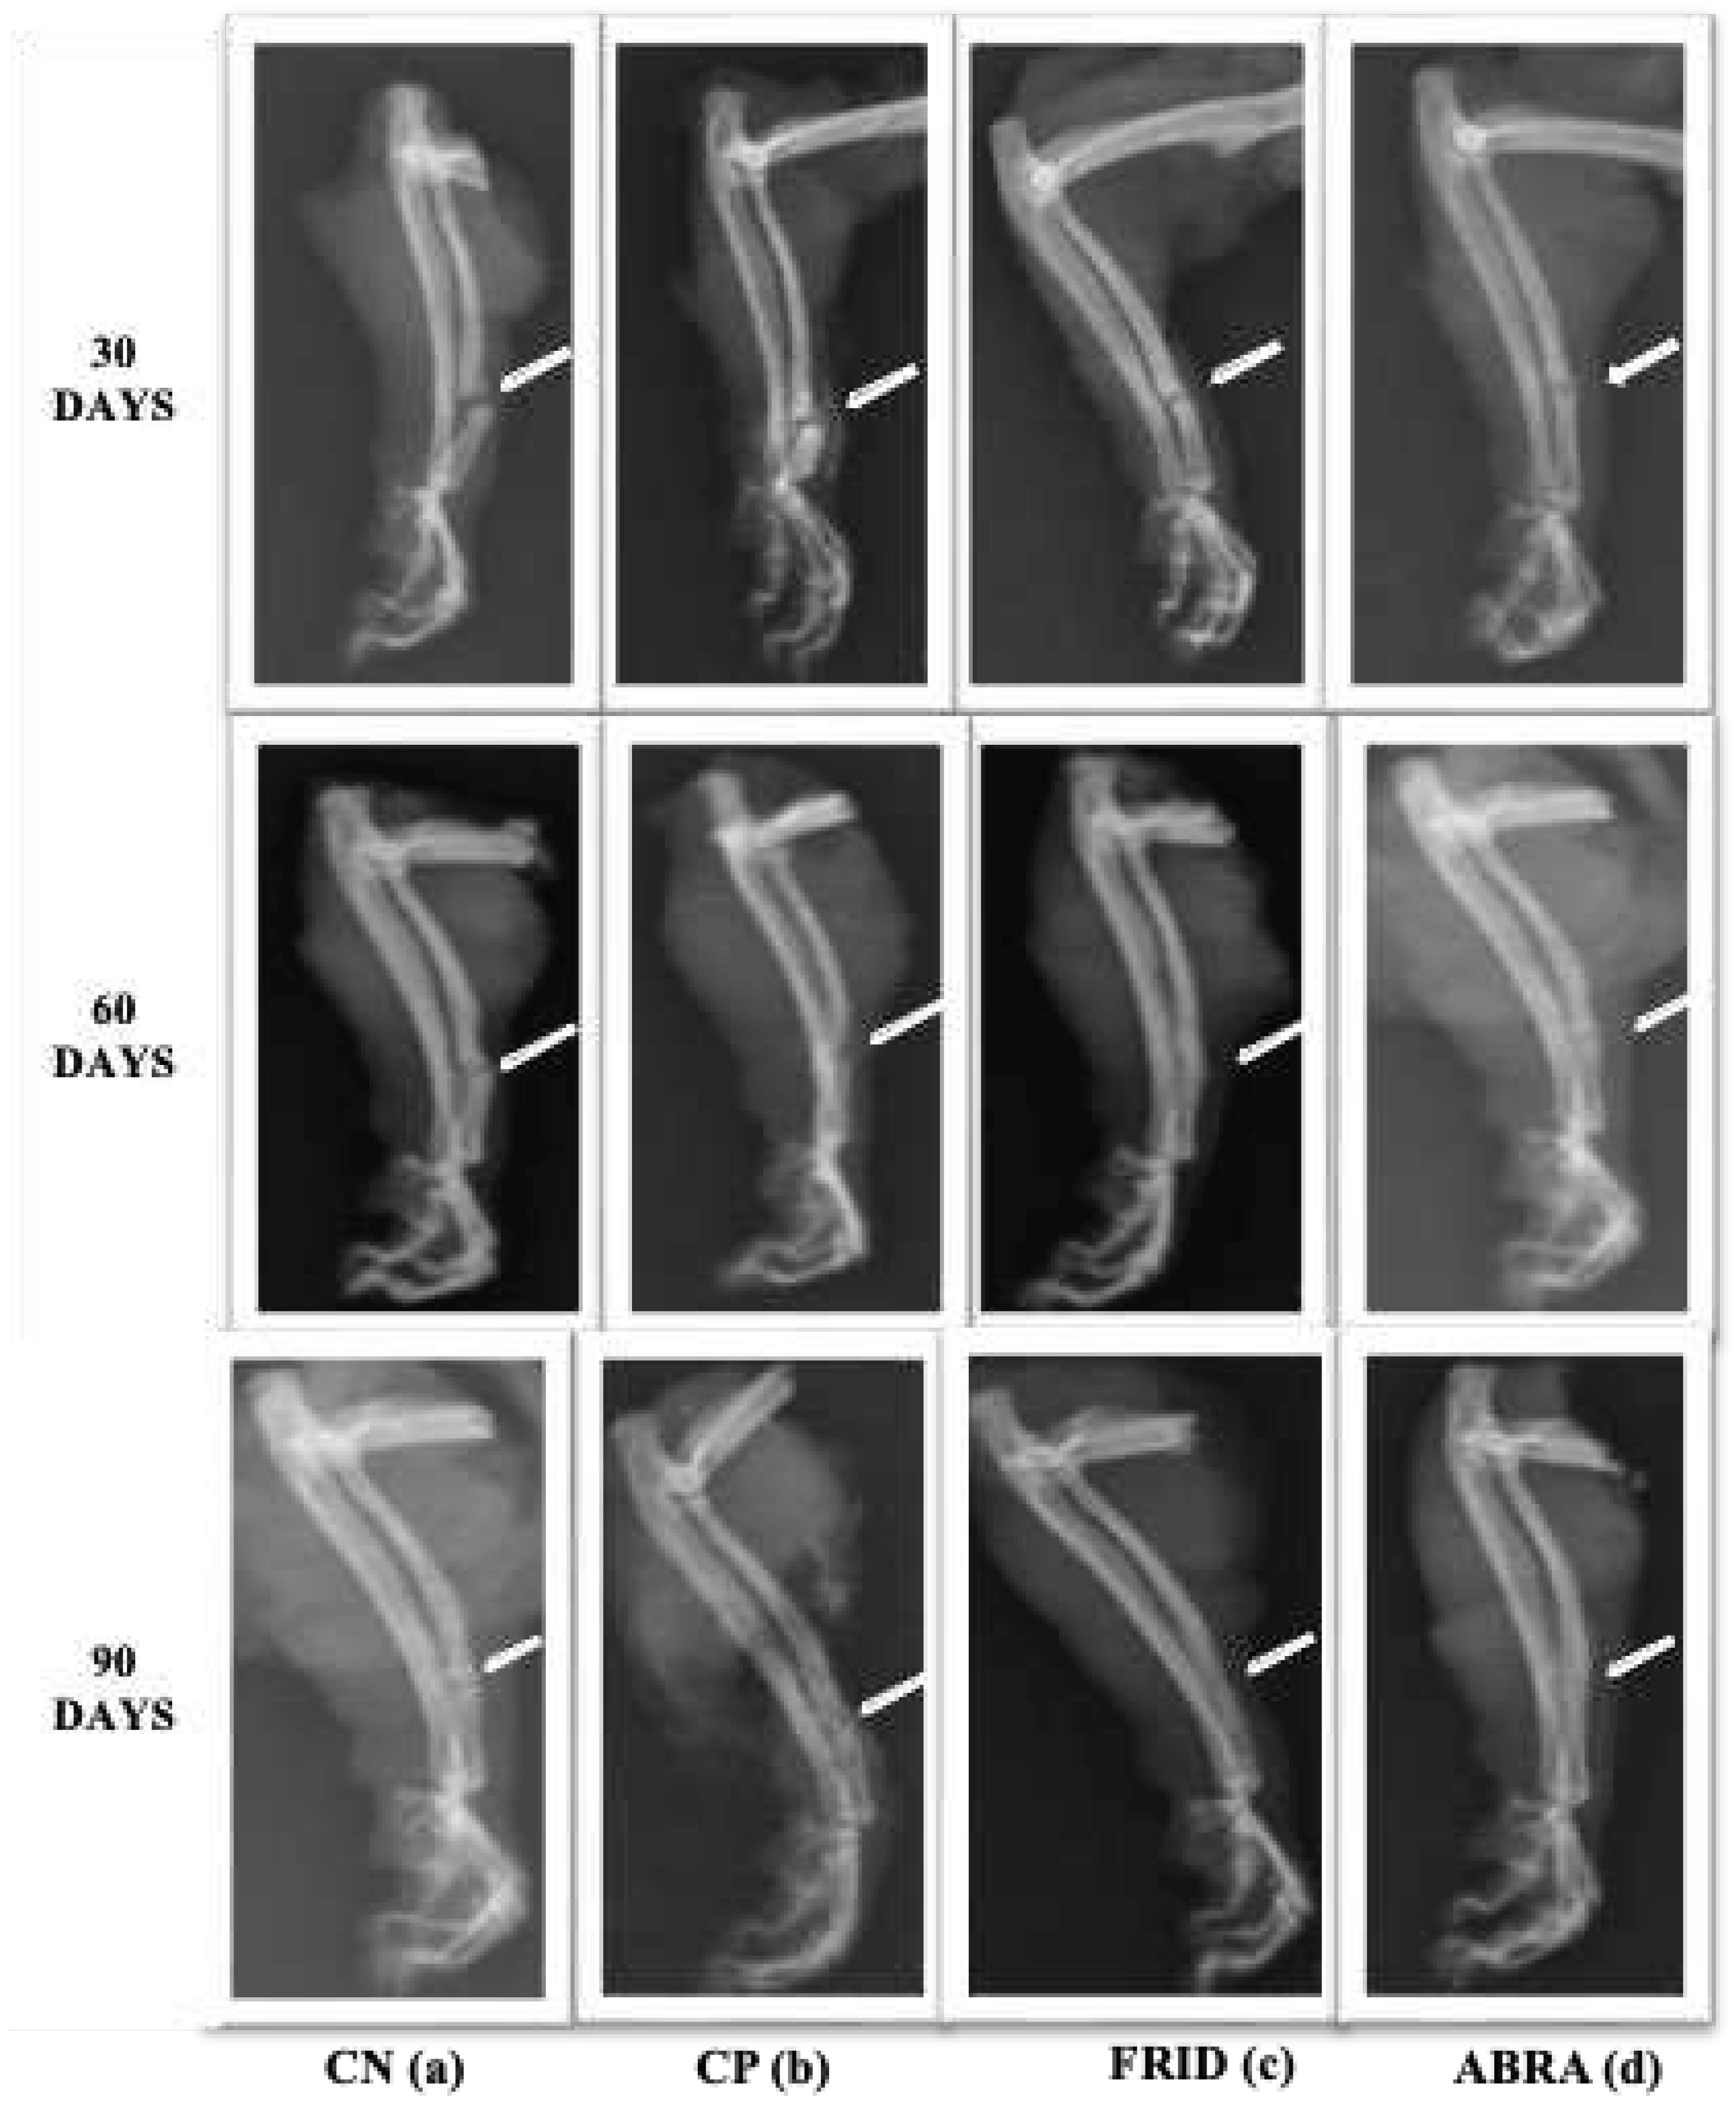

3.5. Fracture Area Radiographic Analysis

There was no statistical difference in fracture line between the control groups studied (

Table 4). The FRID and ABRA groups had improved fracture closure lines at 90 days compared to the others, especially the FRID group, seen right after 60 days (p< 0.05;

Figure 4).

The periosteal reaction was similar between control groups (

Figure 4). A statistical difference was observed (p<0.05) for FRID and ABRA as bone healing progressed. The ABRA group, in particular, showed a higher periosteal reaction after 30 days (

Table 4).

At 30 days FRID group had higher scores, and at 60 and 90 days, the bone callus scores remained elevated for both the FRID and ABRA groups (p<0.05,

Table 4). At 90 days, a higher rate of bone remodeling was observed for the FRID and ABRA groups (

The data from the upper table can be visually observed by radiographic evaluation in

Figure 4 below.

Figure 4.

Line 1: X-ray of rats grafted with chitosan gel (negative control, NC), bovine bone powder (positive control, PC), F. platyphylla graft (FRID), and A. brasiliana graft (ABRA) at 30 days. (a) and (b) – Evident fracture of the alveolar cleft with bone axis deviation, minimal periosteal reaction. (c) and (d) – Presence of fracture line with periosteal reaction and initiation of bone callus formation. Line 2: X-ray at 60 days. (a) – Presence of fracture line, minimal periosteal reaction, and beginning of bone callus formation. (b) - Deviation of the bone axis with fracture line (c) - Minimal fracture line, mild periosteal reaction, bone callus, and bone remodeling process. (d) – Fracture line present, absence of periosteal reaction, bone callus formation, and initial bone remodeling. Line 3: X-ray at 90 days. (a) –Fracture line, periosteal reaction, the beginning of bone callus formation, and bone remodeling. (b) – Absence of fracture line, absence of periosteal reaction, the beginning of bone callus formation, and bone remodeling. (c) – Absence of fracture line, absence of periosteal reaction, bone callus, and bone remodeling process present. (d) – Fracture line absent, absence of periosteal reaction, bone callus and bone remodeling process present.

4.1. Radiographic analysis

Callus and bone remodeling were observed in the ABRA and FRID grafts at 90 days. The reduced volume of calluses and the remodeling process indicate bone calluses' maturity, advanced healing, and restoration of pre-fracture properties. (Pinheiro Neto et al., 2015) observed similar findings on radius bone fractures in rabbits with an aqueous graft of Chenopodium ambrosioides. Acceleration of fracture healing, fracture line absence at 90 days, and bone remodeling are all indicators of complete bone healing. Plant material inducing the recovery of femoral fractures in rats was seen in other studies (Bigham-Sadegh et al., 2018; Estai et al., 2011; Florence et al., 2017).